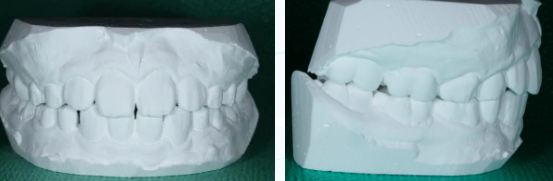

先月定期検診で来院したときの歯並びはこちら☆☆☆

とってもきれいな歯並びになりました!!!!その顔は、とっても自信たっぷり☆彡

歯並びがきれいになると、自信も出てくるんですね!!